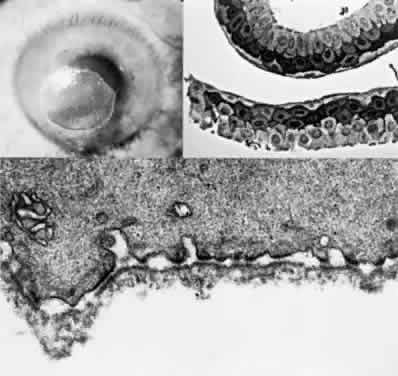

OCULAR FINDINGS. The outstanding clinical feature common to all three phenotypes is the corneal and conjunctival cystine crystal deposition (Figs. 3 and 4). Photophobia is often the only presenting visual symptom; this may be incapacitating and associated with blepharospasm.

Fig. 3. Cystinosis. Refractile crystals noted throughout the corneal stroma.

Fig. 4. Cystinosis. Top, Transmission electron micrograph showing a stromal keratocyte containing a number of needle-shaped crystalline profiles limited by unit membranes. (× 19,000.) Bottom, Electron micrograph of conjunctival fibrocyte revealing crystalline profiles of sparse granular material within membrane-limited lysosomes. (× 30,000.) (Courtesy of Dr. Kenneth Kenyon)

Corneal deposits appear as a layer of homogeneously distributed, fusiform or needle-shaped, iridescent crystals situated in the stroma beneath the epithelium. In the infantile form, anterior crystal deposition begins early in life (between 6 and 15 months of age) and proceeds posteriorly as the patient ages; deposition advances more rapidly in the periphery. The anterior location of the crystals may be associated with recurrent erosions.33 The depth of the stromal deposition and the density of crystals is always greater peripherally than centrally. More and larger crystals occur in the superficial stroma. No visual impairment occurs at this early stage. By the age of 7 years, most patients have crystals, either within or on the endothelial surface34,35; markedly decreased corneal sensitivity is also present.36 The spherical contrast sensitivity function is significantly lower in infantile cystinosis than in age-matched controls.37